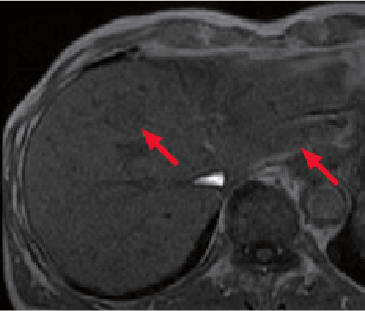

In liver S4 and S2, nodules (→) were found that showed low signals in T1-weighted imaging (g, h), and high signals in fat-suppressed T2-weighted imaging (i), and diffusion-weighted imaging (b value = 1000 s/mm2; j).

With Gadoxetate disodium(Gd-EOB-DTPA) contrast MRI, these nodules (→) showed high signals in the arterial phase (k), and low signals in the hepatobiliary phase (l). The diameters were 2.5 cm for the S4 nodule, and 1.4 cm for the S2 nodule.

On the basis of these findings, the S4 and S2 nodules (→) were diagnosed as moderately to highly differentiated HCC.